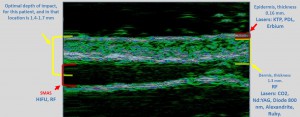

-Υπέρηχος Υψηλής Συχνότητας (HFUS) και Ιστολογία

-Μέθοδοι θεραπείας υψηλής ενέργειας

(λέιζερ, RF-Ραδιοσυχνότητα, HIFU-Υψηλής Έντασης Εστιασμένος Υπέρηχος, κ.λπ.)